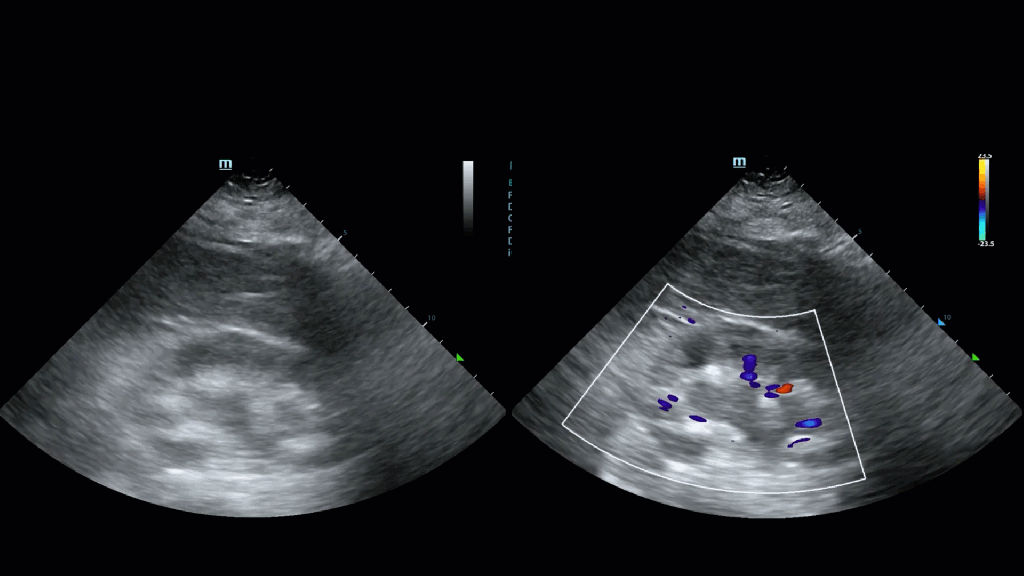

Prominent renal vessels: It is very common to be able to see the renal veins/arteries of the kidney . The is issue is the larger vessels traverse adjacent to the collecting system and can look quite convincing for hydronephrosis as the clip on the left shows. NB (yes there is free fluid as well)

This can be readily resolved by applying colour Doppler over the vessels (ensure the scale is set to 20 cm/s or below as these are not high velocity flows) and if flow is demonstrated it is not urinary stasis. In the images below the central anechoic stripe signalled by the green arrow on the left could be mistaken for low grade hydronephrosis but apply colour we see right away it is a vessel.